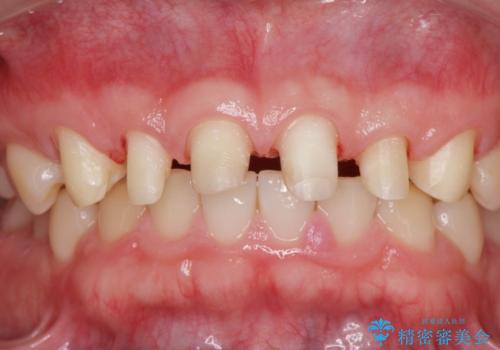

歯周外科を行い、歯ぐきの状態を整えた前歯セラミック治療

- 「前歯の見た目、歯ぐきの腫れを改善したい。」と希望され来院されました。

前歯には接着性の維持装置や、中途半端な形の連結クラウンが装着され、清掃性が悪く歯ぐきの腫れや、歯ぐきの形態の不揃いが認められました。

ただ、白いオールセラミッククラウンを製作・装着するのではなく、将来にわたり安定した状況を獲得するため、歯周外科を行い歯ぐきと周囲の歯槽骨の形態を整えていきます。